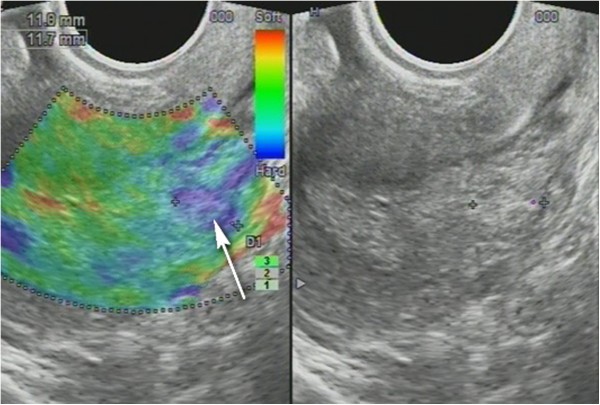

Non-homogenous and irregular margins were significantly higher in AEH than in both groups (P < 0.01). Mean M-echo thickness was found to be non-significant. Hypoechoic areas, hypervascularity on Doppler imaging, and stiffness (Figures 14 and 15) were more specific for AEH than for glandular cystic hyperplasia (P < 0.01, P < 0.01, P < 0.01, respectively; Figure 16). Fluid in the uterine cavity and BGR artefact were found to be specific for AEH (P < 0.01; Figure 17); BGR appearance correlated to the presence of fluid in the uterine cavity (r > 0.97; Figure 18).

Figure 14

Endometrial polyp ( P ). (A) Stiff polyps on SEG, arrow indicates invisible polyp in grey scale that was detected on SEG; (B) Dopplerography of polyp vessel, RI = 0.7.

Figure 15

Sonoelastography of endometrial lesion. Soft pattern on SEG helps to exclude the polyp.